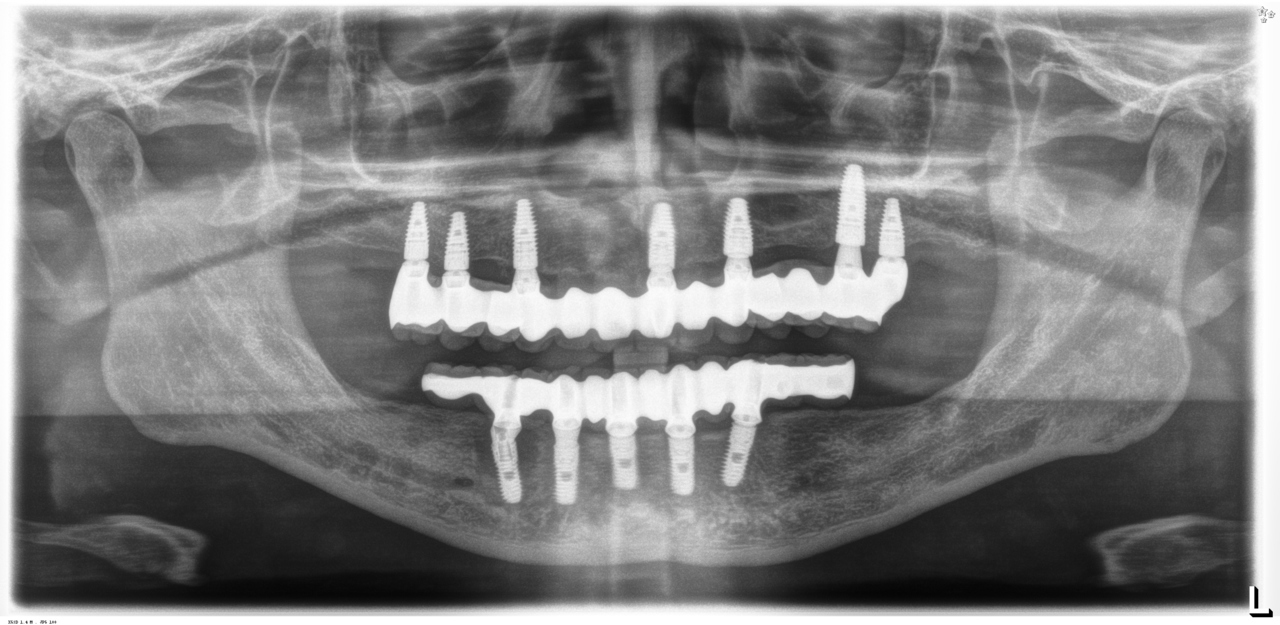

完成後のレントゲン写真

最終的な被せ物を装着した状態のレントゲン写真。

(今回は下顎ですが、その前に上顎は治療済みです。)

5本のインプラントで、12本の歯を並べる(下顎・仮歯代含む)

(御殿場市在住 男性)

お口の中の状態

レントゲン写真

下顎に限定ですが条件が揃えば、5本のインプラントを埋入し、奥に延長した形で、第一大臼歯までを並べることができます。